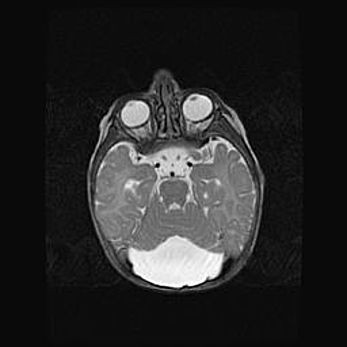

Подострая гематома правой гемисферы мозжечка.

Наружная гидроцефалия.

Возраст: 15 дней

Вес: 3100 г

Пол: женский

Окружность головы: 37 см

Срок гестации: 35-36 недель

При открытой наружной форме гидроцефалии у новорожденных расширяются и переполняются субарахноидные пространства.

Кровоизлияния в мозжечок имеют две клинико-анатомические формы: полушарные гематомы и кровоизлияния в червь.

К появлению этой патологии может привести: повреждения головного мозга, возникающие в результате асфиксии и гипоксии плода при беременности, или травмы во время родов. Редко гематома мозжечка может быть результатом первичной коагулопатии и сосудистой мальформации, диссеминированном внутрисосудистом свертывании, изоиммунной тромбоцитопении.